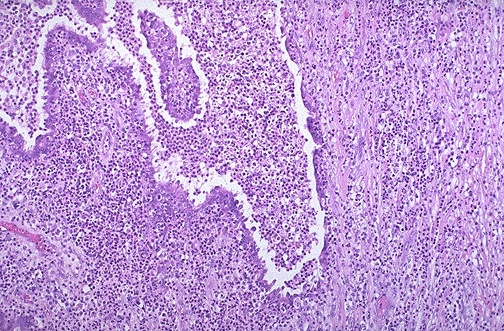

The medium power microscopic appearance of the fallopian tube is shown here.